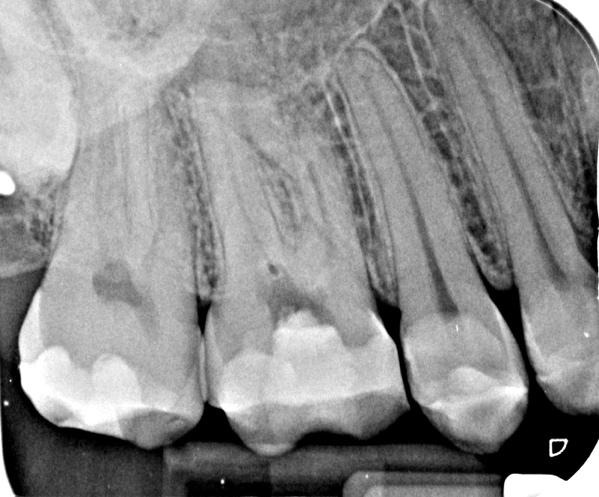

Diagnosis

Pulp necrosis with no clear apical change on IOPA